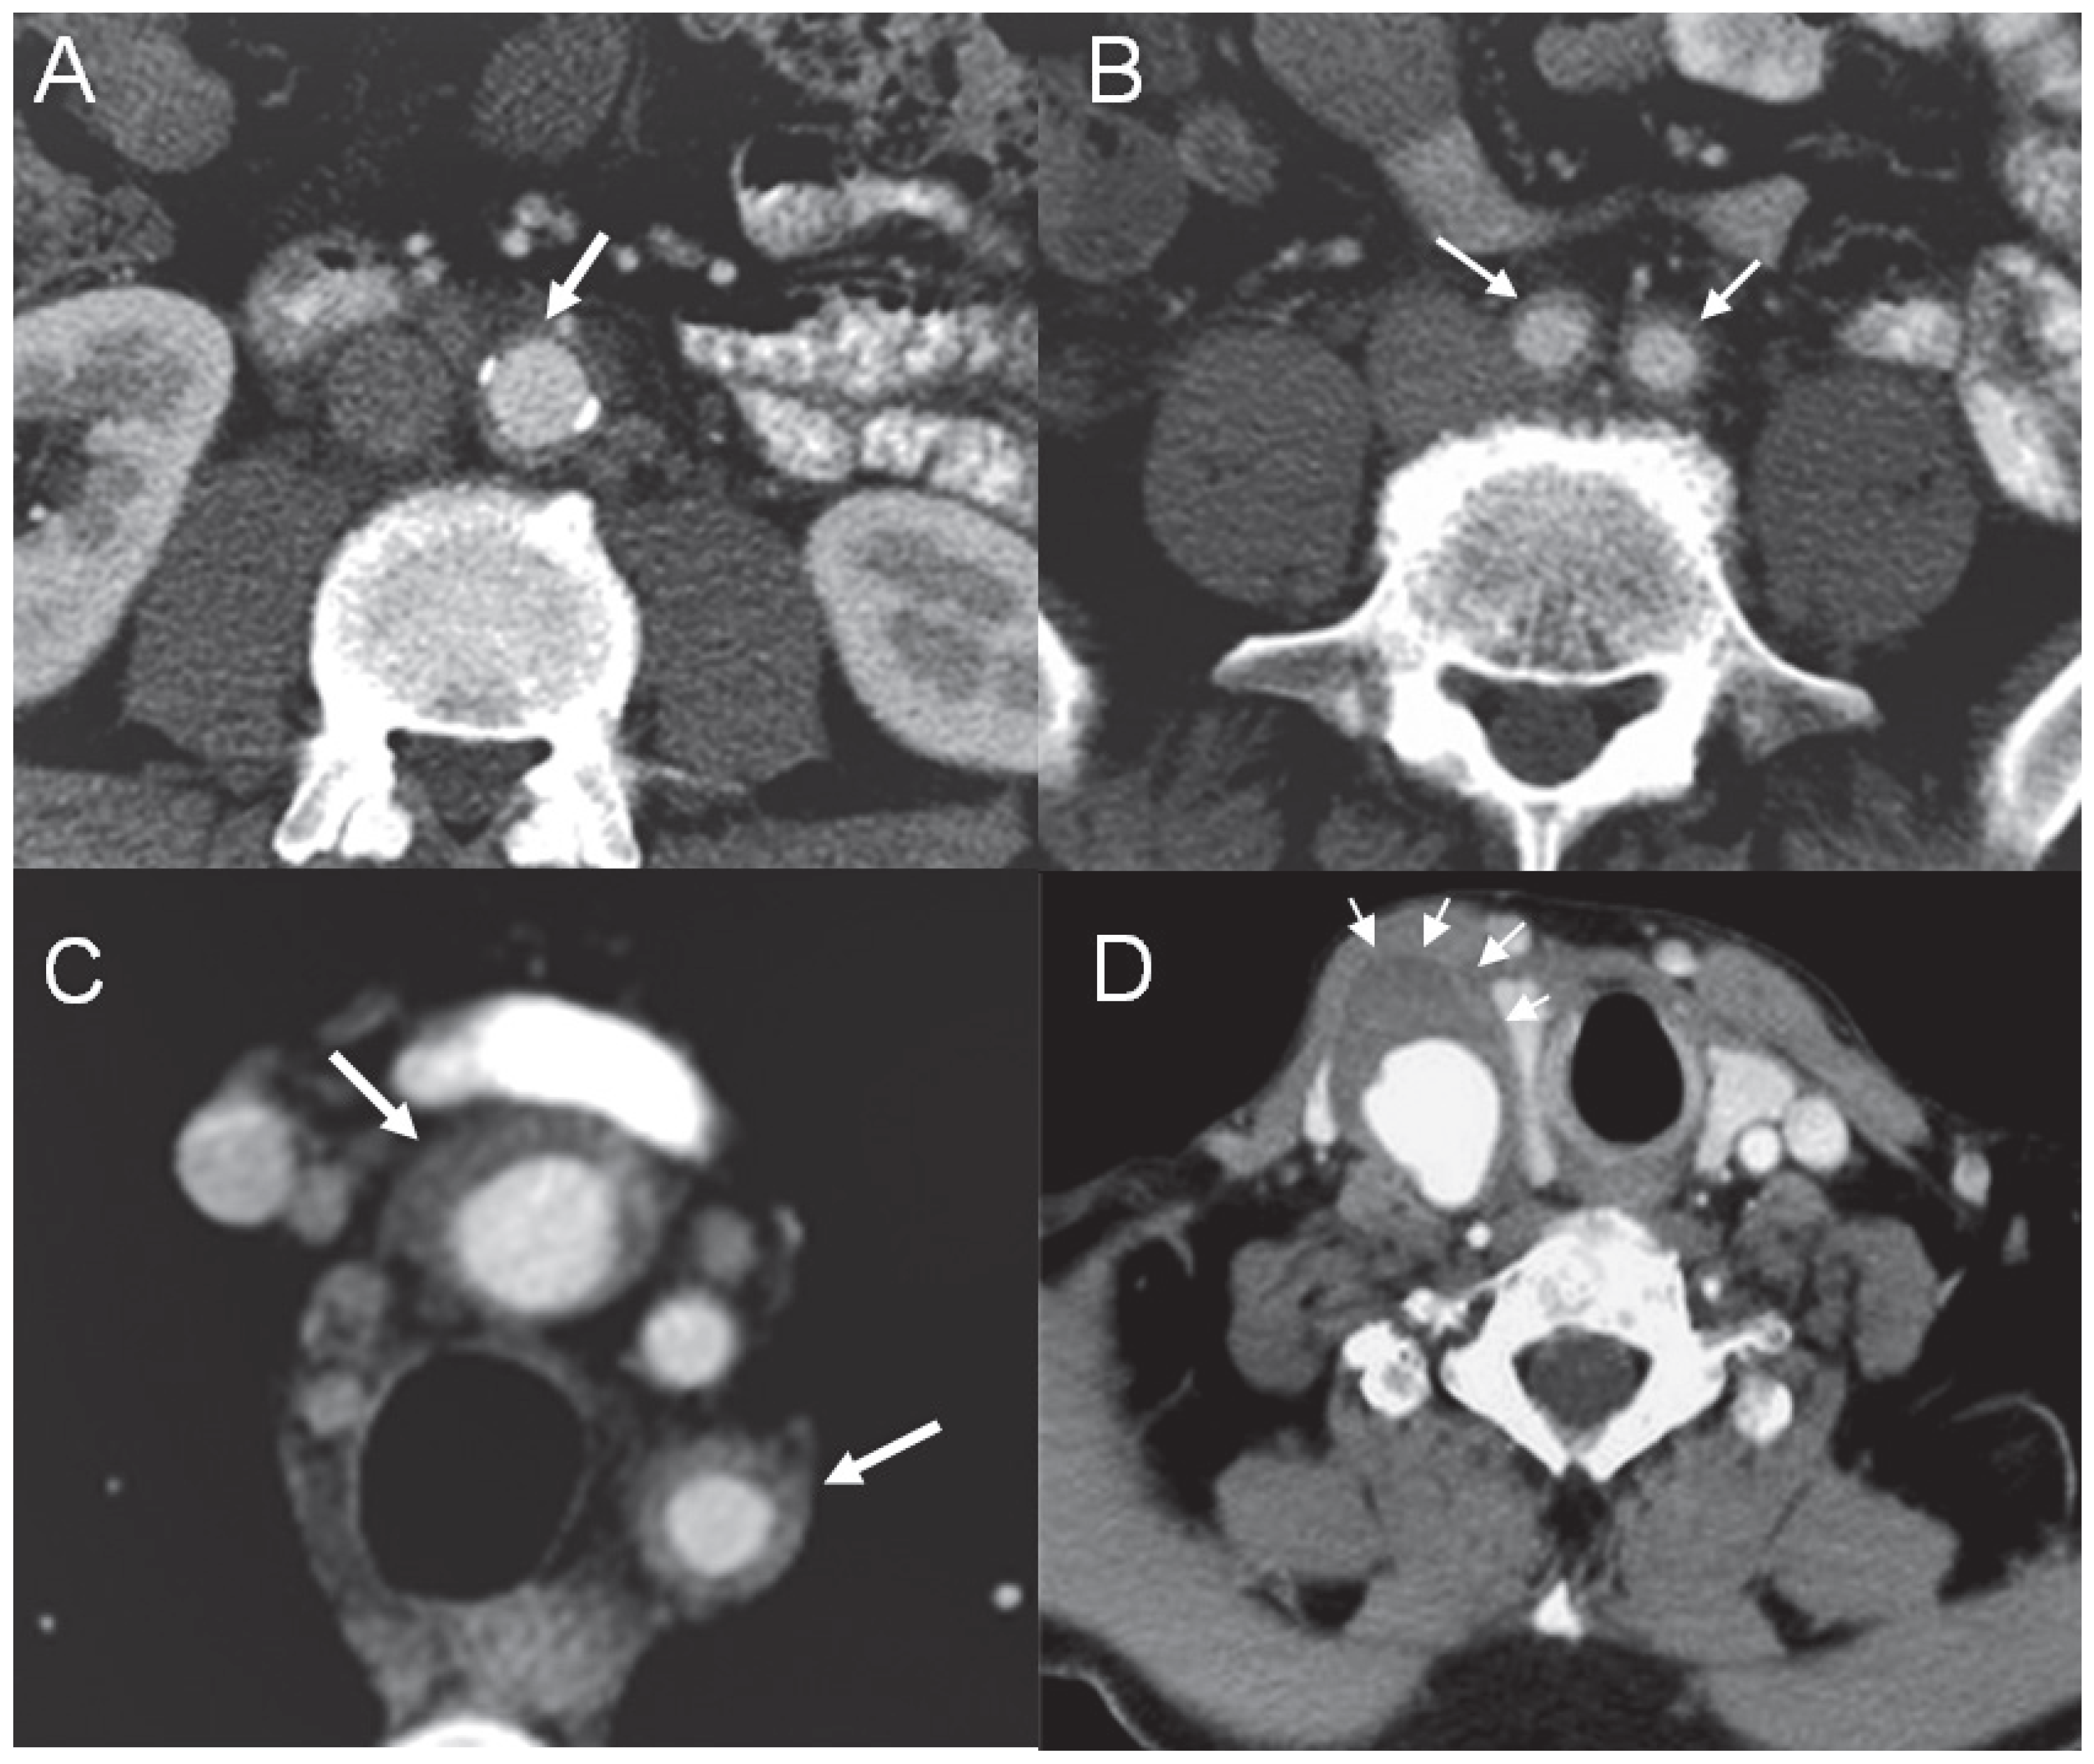

Figure 2.

Abdominal aortic wall thickening (A) with involvement of the iliac arteries (B) and epiaortic branches (C). CT angiography showing the aneurysm of the right common carotid artery with thickening of the wall and suspected thrombus (D).

Therapy with steroids, mycophenolate and cyclosporin did not result in a desirable improvement. On the basis of the fact that PG was responsive to local tacrolimus, the probative treatment with oral tacrolimus at a dosage of 3 mg/b.i.d., on top of steroids and mycophenolate, was attempted. It resulted in a rapid clinical improvement and regression of inflammation documented with 18FDG PET after four months. Six months later, the patient presented with pain in the right supraclavicular region and presence of a pulsating tumour. CT angiography revealed an aneurysm of the innominate artery (maximal diameter of 24 mm) expanding to the right carotid commune artery (maximal dimensions of 24 × 33 mm) with wall thickening and suspected thrombus adherent to the wall of the aneurysm (Figure 2, panel D). Mild dilatation of the ascending aorta (44 mm), not observed on the previous CT scan, was also documented. The patient continued immunosuppressive treatment and clopidogrel was introduced. The possibility of endovascular retrograde covered stenting was discussed with the patient. Due to further expansion of the right carotid commune artery aneurysm (increased to maximal dimensions of 35 x 46 mm), the intervention was successfully performed two months later (January 2007) with good positioning of the stent and without signs of leaking (Figure 3). The patient continued immunosuppressive therapy with subsequent periodical radiological and duplex controls. He had two relapses of PG, which required hospitalisation, in the next two years. In 2009, routine echocardiography revealed expansion of the ascending aorta from 44 to 50 mm leading to severe aortic regurgitation, and dilatation of the left ventricle. Coronary angiography was performed and showed a co-lateralised occlusion of the right coronary artery and non-significant plaque in the left anterior descending artery. In November 2009, aortic valve and ascending aorta replacement as well as single aorto-coronary by-pass graft surgery was performed. Histological analysis of an aortic specimen showed degeneration of media, adventitial fibrosis with lymphocyte infiltration. Although these findings were not specific for TA and could be found in other forms of vasculitis, it is known that a negative biopsy does not definitely rule out the diagnosis of TA.

A 52-year-old male was admitted to our hospital with a fever of unknown origin and raised inflammatory parameters (CRP 251 mg/l, ESR 50 mm/h) in March 2006. He had a history of recurrent pyoderma gangrenosum (PG) of the lower extremities since the age of 14 years old. After numerous attempts with various immunosuppressive agents, stable remission was finally achieved using local tacrolimus applications (Figure 1). Physical examination except for scarring after PG lesions in the lower limbs was otherwise unremarkable. To search for the possible causes of inflammatory syndrome thoraco-abdominal computed tomography (CT) was performed. It revealed thoracic and abdominal aortic wall thickening (Figure 2, panel A) with involvement of epiaortic branches (Figure 2, panel C), the coeliac trunk, the superior mesenteric artery and iliac arteries (Figure 2, panel B). 18FDG positron emission tomography (PET) revealed the presence of active inflammatory aortic wall processes at the level of the thoracic and abdominal aorta as well as the aortic arch branches, the left coronary artery and the iliac arteries. The duplex scan of the temporal arteries was negative for the signs of giant cell arteritis (GCA), and the patient did not present any typical clinical signs of this vasculitis (e.g., localised headache, visual disturbance, tenderness of the temporal artery or jaw muscle pain). Therefore, radiological findings of large vessel vasculitis without evidence of other inflammatory disorders (ANCA, ANA, HLA B5, HLA B25 negative) in association with PG made the diagnosis of Takayasu arteritis (TA) the most likely one.